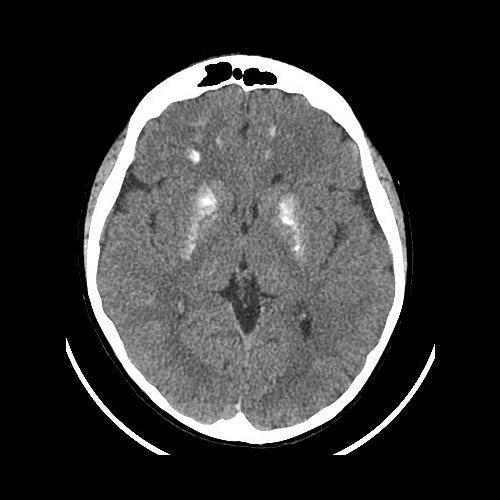

Noviembre 2021. Consultorio Conci Carpinella Paciente masculino de 10 años de edad que consulta por convulsiones.